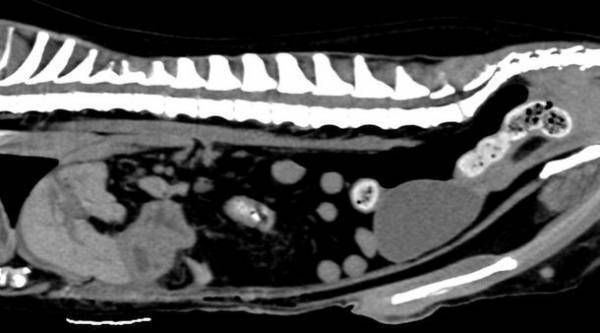

■CT検査

X線を用いて対象を360度方向から連続的に撮影することで全身の断層像を短時間で得ることができます。

CT検査画像

GE社製 64列128slice CT装置 Revoluion EVO

■CT検査

X線を用いて対象を360度方向から連続的に撮影することで全身の断層像を短時間で得ることができます。

得られる情報は非常に多く、悪性腫瘍の浸潤範囲や転移検索、臓器の形態的異常などを詳細に評価することができます。

CT検査画像

GE社製 64列128slice CT装置 Revoluion EVO